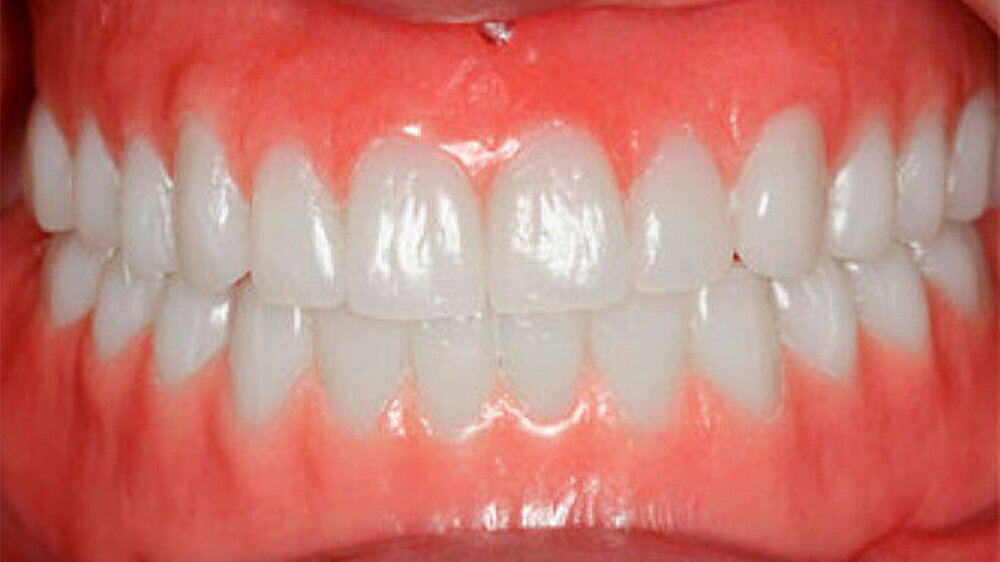

Aufgrund des anatomisch sehr ungünstigen Prothesenlagers war der Erhalt der Restbezahnung im Oberkiefer anzustreben. Nach Kariesexkavation und Wurzelkanalbehandlung konnten beide Zähne mit einer Wurzelstiftkappe versorgt und die alten Prothesen entsprechend umgebaut werden. Im Anschluss an die Meisterabformungen und an die Ausrichtung der Wachswälle wurden die Modelle schädelbezogen einartikuliert, und die Prothesenzähne nach ästhetischen und funktionellen Richtlinien aufgestellt. Eine bilateral balancierte Okklusionsbeziehung konnte umgesetzt werden. Im Oberkiefer wurde eine gerüstverstärkte Totalprothese hergestellt, die auf den beiden Wurzelstiftkappen 16 und 26 verankert war. Im Unterkiefer konnte die Patientin mit einer Totalprothese versorgt werden (Abb. 21 bis 23).